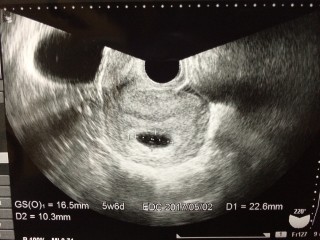

理想的なダイヤモンドリングが見えて感動しました。5w6dで既に心拍も確認できホッとしました。大きさはGS22mm, CRL2.7mmでした。